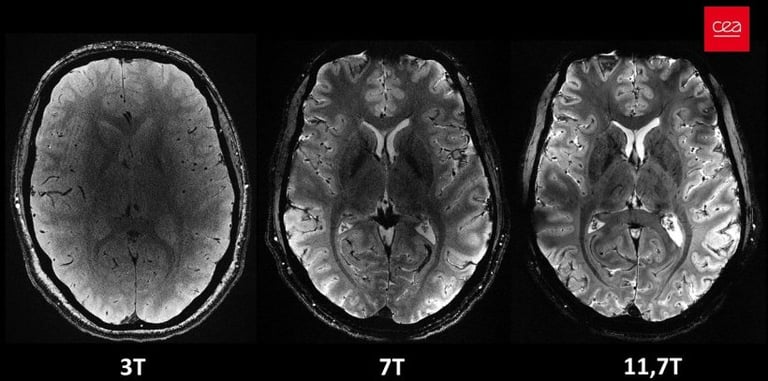

Just about four minutes. That’s all it took to acquire some of the most remarkable anatomical images of the brain from participants in the first study involving the Iseult MRI machine. The scanner, which uses magnetic resonance imaging technology, has a magnetic field intensity of 11.7 teslas, making it the most powerful in the world. The images have an impressive resolution for such a short acquisition time – 0.2 mm in-plane resolution and 1 mm slice thickness, which represents a volume equivalent to a few thousand neurons. For comparison, the same image quality would require hours with MRI scanners currently available in hospitals (1.5 or 3 teslas). This is not realistic in practice as patients would not be comfortable and any movement would “blur” the image.

11.7 Tesla: First images from the world's most powerful MRI scanner

The French Alternative Energies and Atomic Energy Commission (CEA) is revealing a series of in vivo human brain images acquired with the Iseult MRI machine and its unmatched 11.7 teslas magnetic field strength.